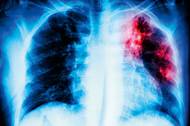

Uprchlíci za tuberkulózu nemohou